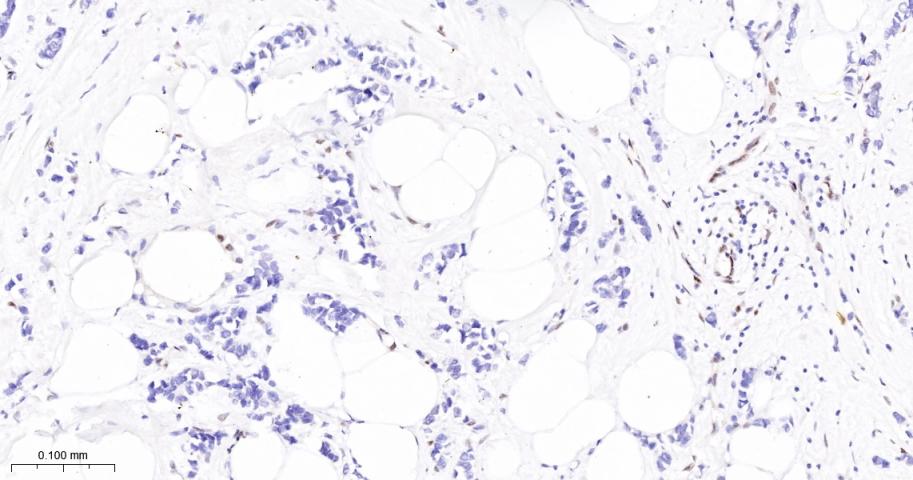

Paraformaldehyde-fixed, paraffin embedded Mouse Uterus; Antigen retrieval by boiling in sodium citrate buffer (pH6.0) for 15 min; The section was incubated with JUNB Monoclonal Antibody, Unconjugated (bsm-60454R) at 1:200 overnight at 4°C, followed by conjugation to the bs-0295G-HRP and DAB (C-0010) staining.